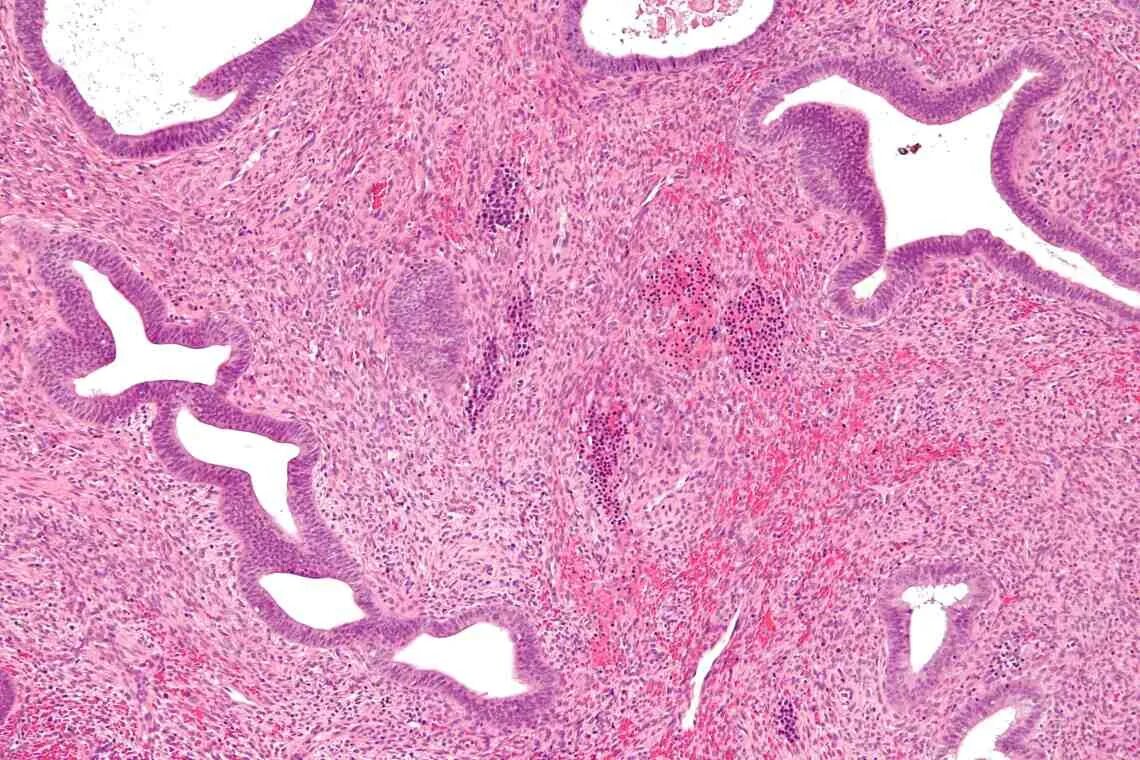

Гистологическое исследование полипа